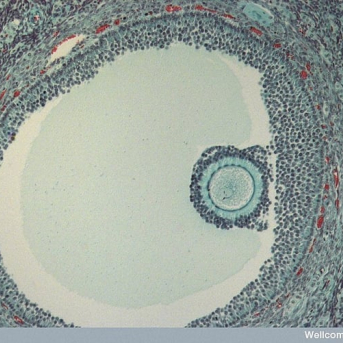

O teste de ovulação basicamente detecta um hormônio em abundância que faz o folículo romper e o óvulo sair para as trompas. O LH, hormônio luteinizante, em seus picos são capturados pelos anticorpos e reagentes existentes na tira de teste e fazem com que a linha de teste fique mais escura ou da mesma cor que a linha de controle. Caso a linha fique clara, então é sinal que o pico hormonal ainda não ocorreu.